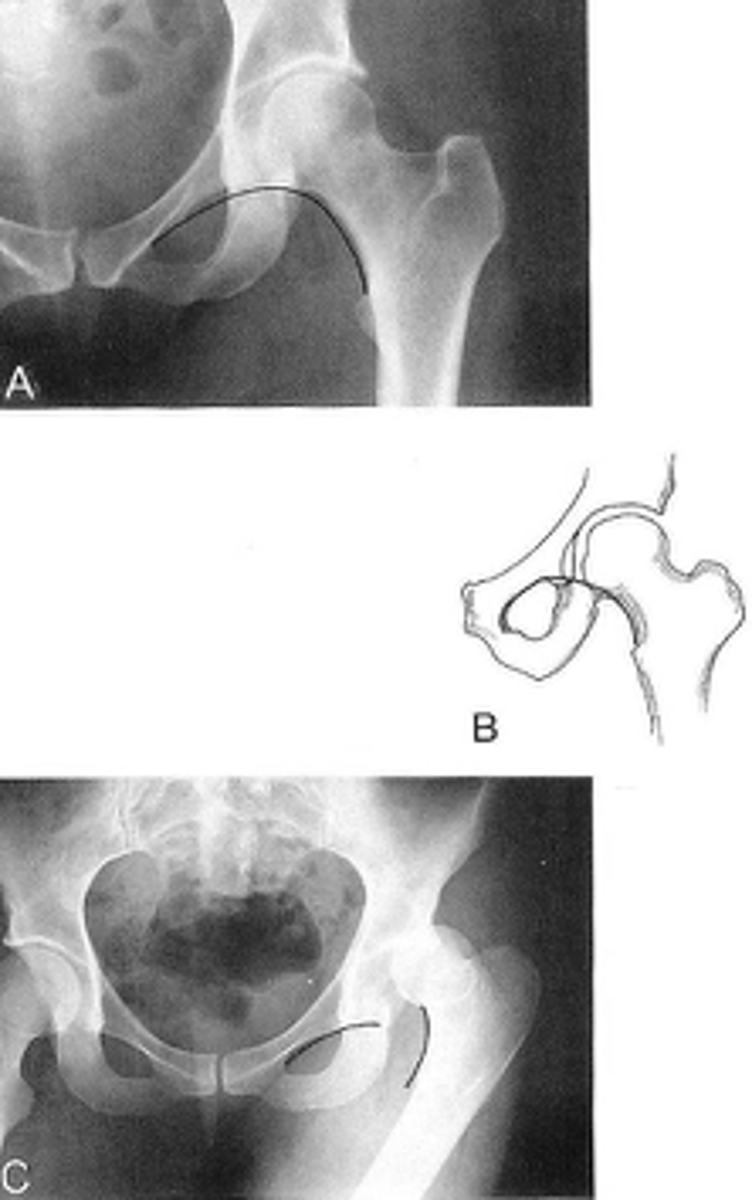

Kohler's teardrop distance

ID measurement line

<p>ID measurement line</p>

- AP pelvis

- AP hip

What views are needed to see Kohler's teardrop distance?

- Medial margin of femoral head

- Lateral border of teardrop

Kohler's teardrop distance landmarks

6-11 mm

Normal Kohler's teardrop distance measurement

2 mm

The normal Kohler's teardrop distance is 6-11 mm, and there should be no greater than a _____ difference when comparing to the contralateral side

Hip joint effusion

Clinical significance of an enlarged Kohler's teardrop distance

Waldenstrom's sign

What sign indicates an enlarged Kohler's teardrop distance?

- Accentutation of the normal limits

Intracapsular swelling/joint effusion

Waldenstrom's sign is usually an indication of _____

Inflammatory arthritis

Clinical significance of a small Kohler's teardrop distance